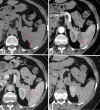

Figure 2. Dynamic contrast-enhanced axial CT examination

On non-contrast axial CT imaging (a), a hypodense mass lesion measuring 26x20 mm with mildly lobulated contours is observed in the inferior spleen (red arrows). On post-contrast images (red arrows), the lesion demonstrates peripheral nodular enhancement during the arterial phase (b) (red asterisks) and progressive centripetal enhancement during the portal phase (c). In the late venous phase images (d), the lesion shows enhancement similar to the surrounding splenic parenchyma.